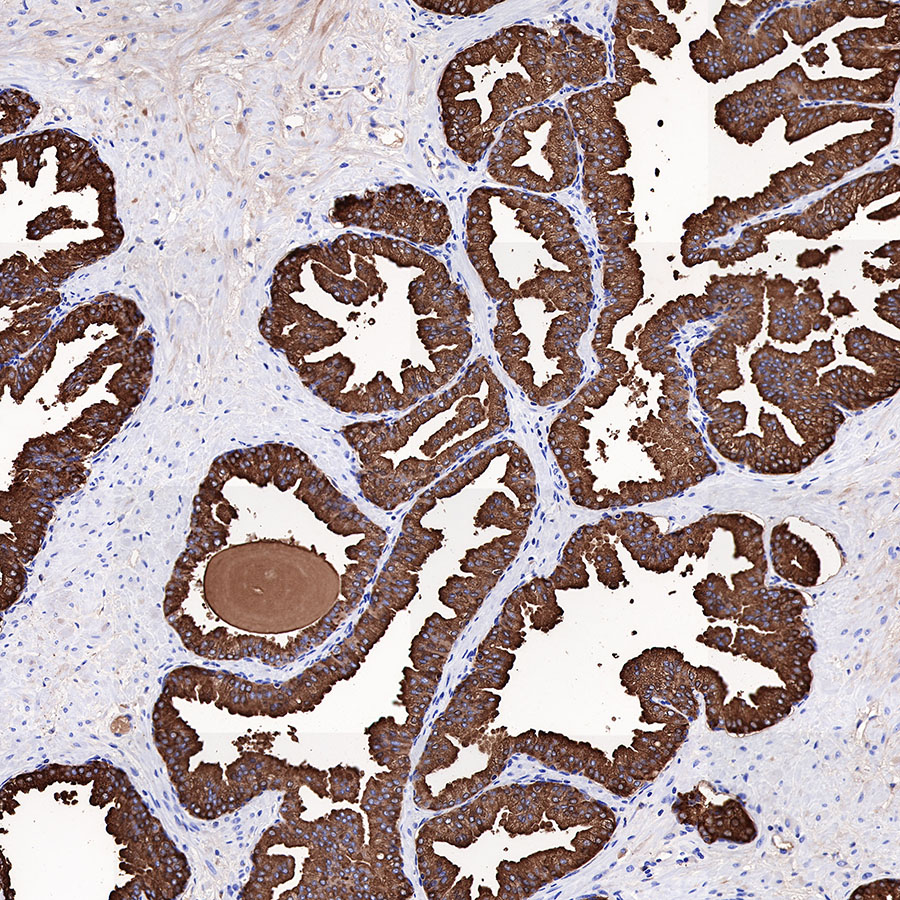

| 病理诊断辅助:经过适当验证后,可用于免疫组化(IHC)检测,辅助前列腺癌的病理诊断与鉴别诊断。 |